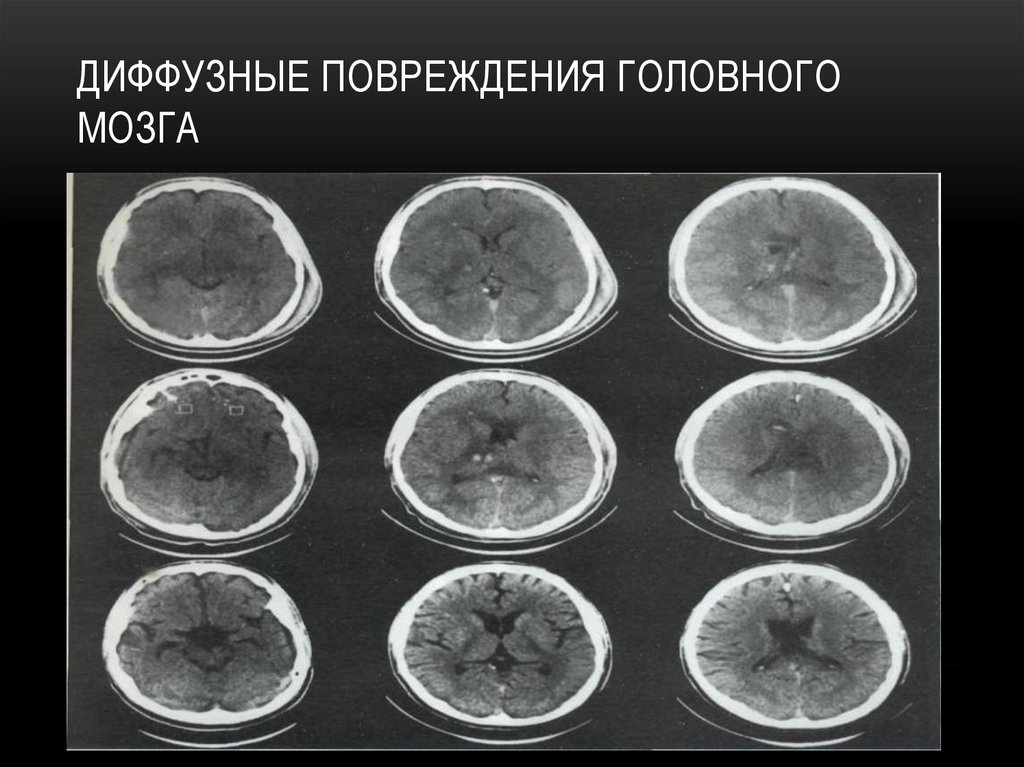

ДИФФУЗНЫЕ ПОВРЕЖДЕНИЯ ГОЛОВНОГО

МОЗГА

КЛАССИФИКАЦИЯ:

-Сотрясение головного мозга

-Диффузное аксональное повреждение

-Травматическое субарахноидальное кровоизлияние